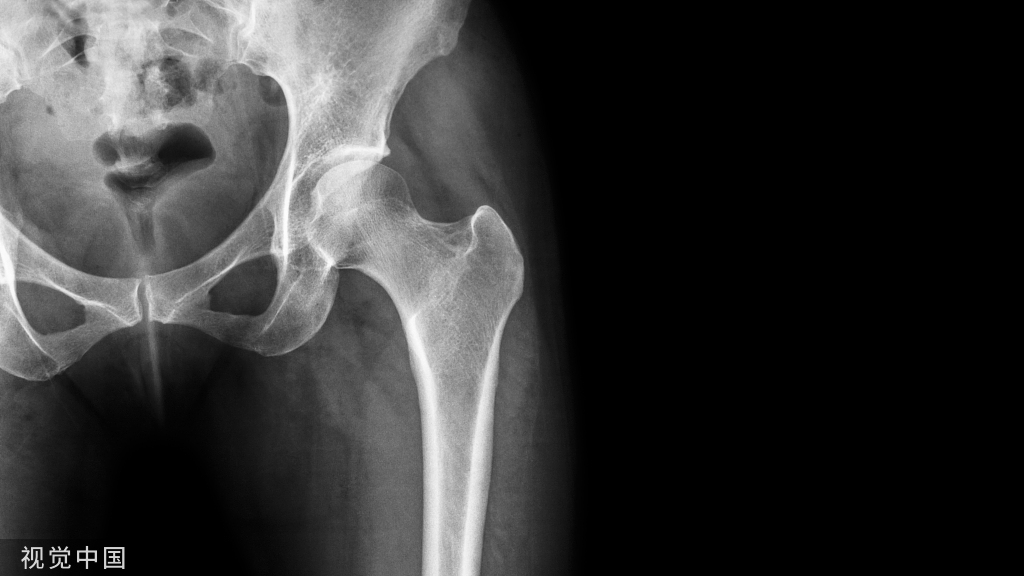

对应的X线表现:

正位

侧位